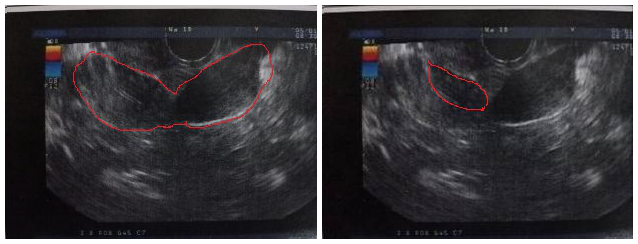

再给小雨复查了一个子宫双附件和泌尿系B超,提示:

双子宫、双宫颈可能,左侧子宫宫腔少量积液,右侧子宫、宫颈管内不均质回声团(41×30mm,透声差,可见密集点状回声)。泌尿系的B超提示右肾缺如。

(左图红色区域为两个子宫影像,右图红色区域为阴道内包块影像)

换句话来说,就是小雨很可能有两个子宫、宫颈及阴道,但却只有左边一个肾。